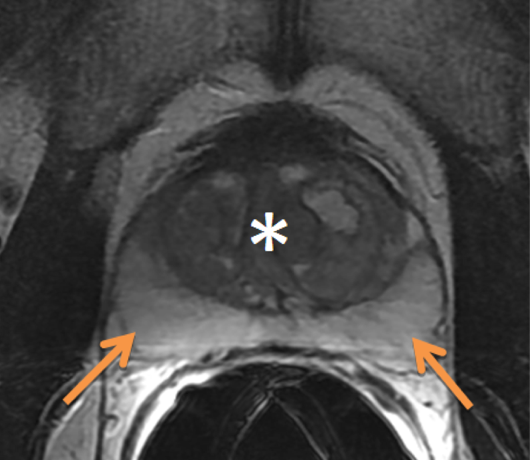

Prior TURP may also be a contraindication as this may allow seeds to overdose the urethra, which could lead to stricture or post-implant incontinence. With modern peripheral loading techniques, this may be less a contraindication than previously thought as complications have decreased. Linked seeds may be advantageous in this setting. Before any brachytherapy in a patient with a history of TURP can be considered, detailed imaging of the extent of TURP should be obtained and considered mandatory. T2 MRI and T1 post gadolinium will be helpful.

This is probably not the ideal prostate candidate for implant.